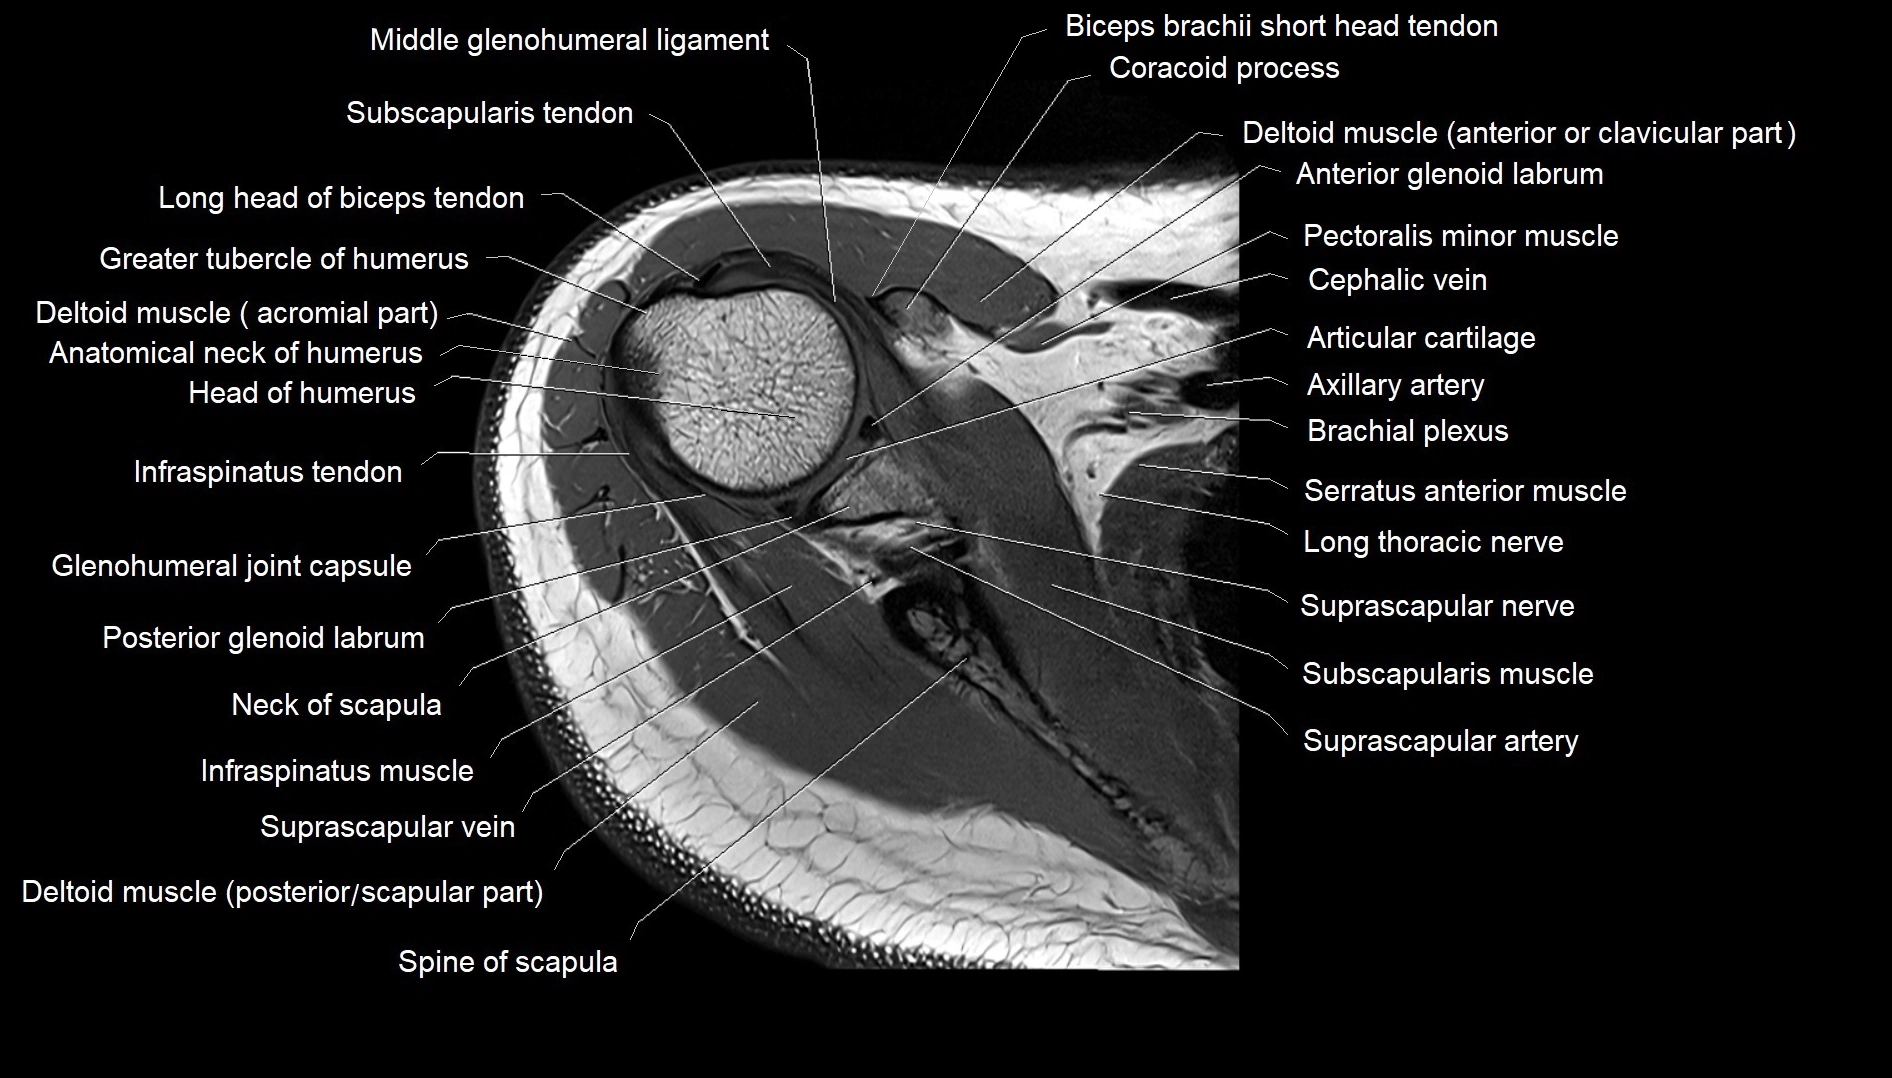

MRI images

image